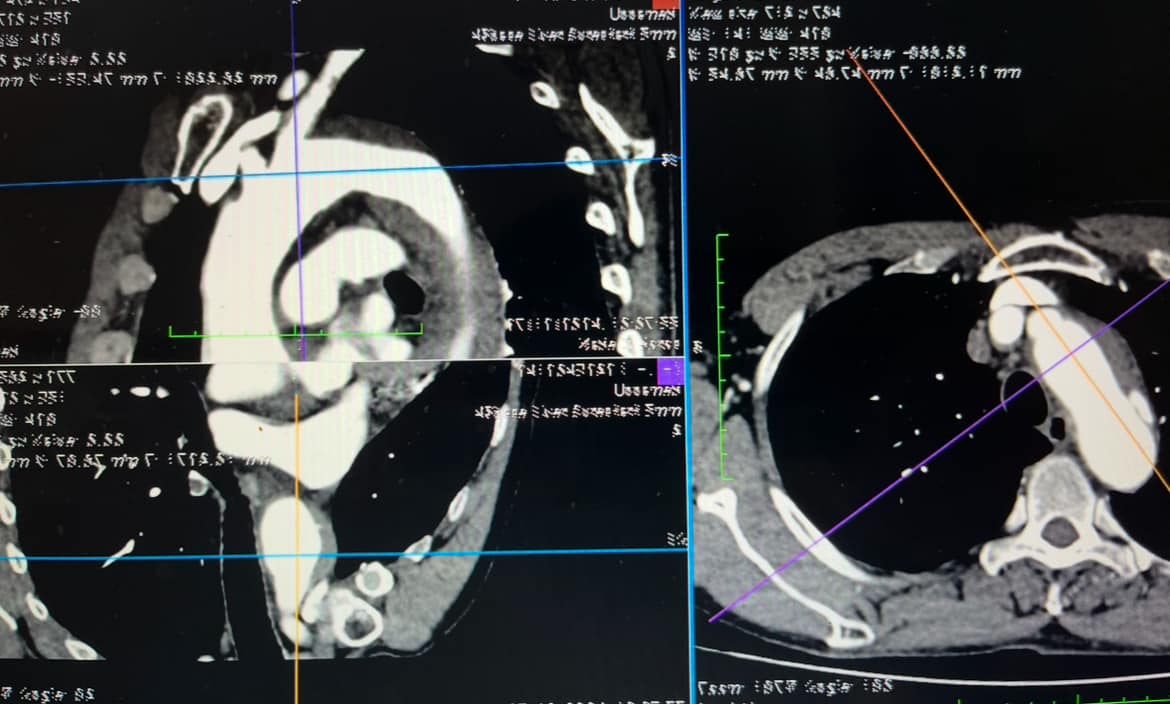

Bệnh nhân N.V.K (68 tuổi, thành phố Thanh Hóa), tiền sử tăng huyết áp, vào viện do đau ngực trái dữ dội, đau sau xương ức, đau như dao đâm, lan ra sau lưng. Qua thăm khám lâm sàng, các bác sĩ khoa Tim mạch đã nghĩ ngay đến đây là tình trạng đau ngực cấp nghi do bệnh lý động mạch chủ ngực. Bệnh nhân ngay sau đó được chụp cắt lớp vi tính động mạch chủ ngực thì phát hiện tổn thương loét xuyên thành động mạch chủ, nguy cơ vỡ rất cao.

Hình ảnh can thiệp của bệnh N.V.K trên máy chụp DSA